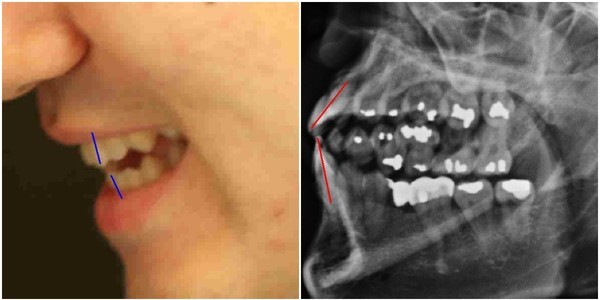

양승오 박사 등은 2012년 2월22일 박주신씨에 대한 공개신검 직후부터 언론을 통해 공개된 주신씨의 허리 부분 MRI 및 주신씨의 치아가 보이는 엑스레이 사진 등을 근거로, 주신씨가 대리신검 혹은 영상자료 바꿔치기 등의 방법으로 병역을 기피했다는 의혹을 제기하고 있다.

- ▲ ▲박주신의 자생병원 X-Ray(왼쪽)과 공군 X-Ray(오른쪽). 자생병원의 엑스레이에서는 오른쪽 제1늑골부위에 '석회화'현상이 보이지만 공군엑스레이에선 보이지 않는다. ⓒ 뉴데일리DB

박주신씨의 자생병원 X-Ray를 보면, 오른쪽 제1 늑골부위에 ‘석회화’ 현상이 나타난다. 그러나 주신씨가 공군 입대 당시 찍은 X-Ray에는 이런 모습이 전혀 보이지 않는다.

이런 차이에 대해 양승오 박사의 변호인인 차기환 변호사 등은 "각각의 X-Ray를 찍은 사람이 동일인이 아니라는 것을 입증한다"고 설명했다.

‘극상돌기’의 경우에도 차이점은 명확히 드러난다.

변호인 측은 “공군에서 찍은 엑스레이와 비자발급을 위해 찍은 엑스레이에서는 피사체의 제 1흉추 극상돌기가 오른쪽으로 휘어있지만, 자생병원에서 찍은 영상에서는 정방향으로 나온다”며, “박주신씨가 공군에 입대해 찍은 엑스레이와 세브란스 공개신검에서 나타난 피사체의 의학적 차이가 명확해 동일인이라고 인정할 수 없다”고 지적했다.

우리가 흔히 등을 만지면, 가운데 뾰족하게 솟아난 부분이 바로 ‘극상돌기’다.

흉추를 비롯해 모든 척추에 존재하며, 흉추에 외상이나 수술, 질병 등이 없었던 근접한 기간 동안 촬영된 엑스레이에서 극상돌기의 형태가 명확하게 다를 경우, 다른 개체라고 판단할 의학적 근거가 된다.